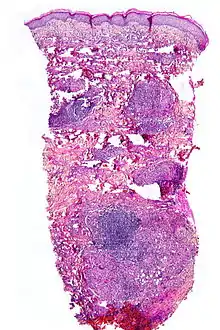

Micrograph showing necrobiosis lipoidica in a punch biopsy

NL is diagnosed by a skin biopsy, demonstrating superficial and deep perivascular and interstitial mixed inflammatory cell infiltrate (including lymphocytes, plasma cells, mononucleated and multinucleated histiocytes, and eosinophils) in the dermis and subcutis, as well as necrotising vasculitis with adjacent necrobiosis and necrosis of adnexal structures. Areas of necrobiosis are often more extensive and less well defined than in granuloma annulare. Presence of lipid in necrobiotic areas may be demonstrated by Sudan stains. Cholesterol clefts, fibrin, and mucin may also be present in areas of necrobiosis. Depending on the severity of the necrobiosis, certain cell types may be more predominant. When a lesion is in its early stages, neutrophils may be present, whereas in later stages of development lymphocytes and histiocytes may be more predominant.